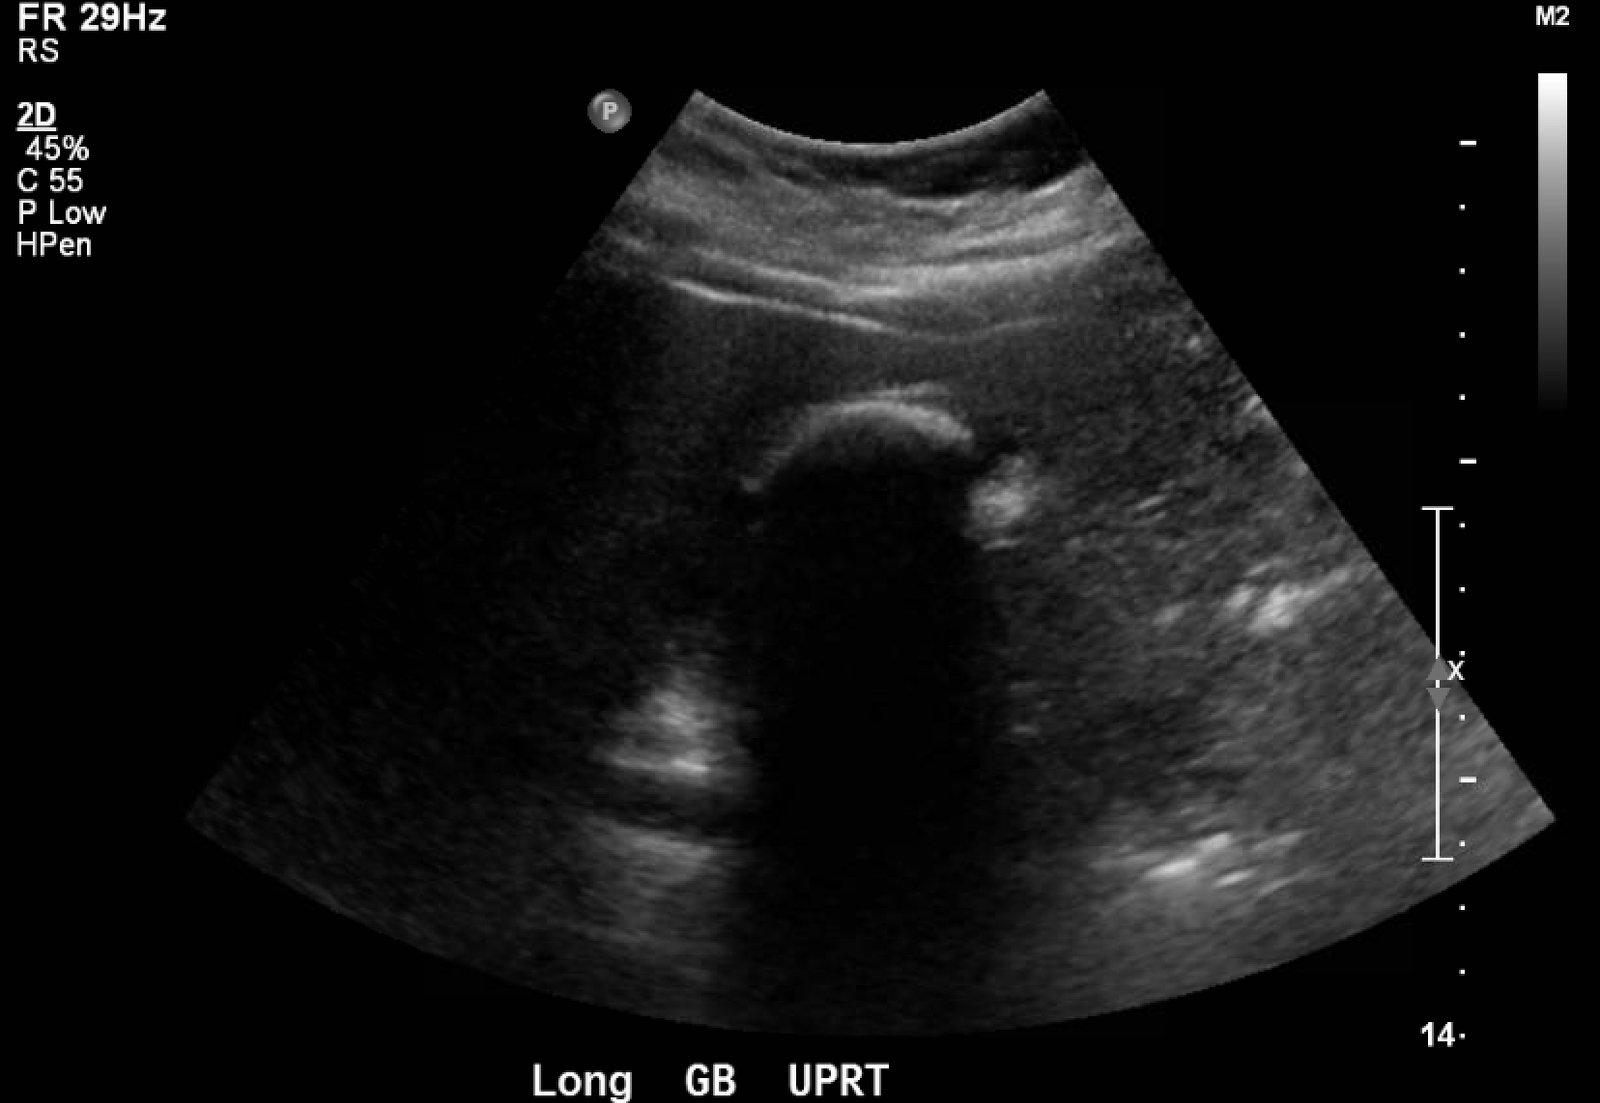

Abdominal ultrasound showed the classic presentation of the Wall-Echo-Shadow (WES) sign. The superficial aspect of the gallbladder wall is represented by a hyperechogenic curve. Below this, bile fluid is represented by hypoechogenicity. Underneath the bile fluid is the echo of the dense border created by the collection of gallstones, represented by a hyperechogenic curve. Due to the high density of the gallstones, nothing deeper can be visualized (including other gallstones or the far end of the gallbladder); this is the shadow.

The WES sign, first described in the early 1980s, is a clear way of identifying cholelithiasis when the condition has progressed to fill the entire lumen of the gallbladder.1 In this case, the lumen of the gallbladder looks hypoechogenic relative to the surrounding tissue, much like an empty gallbladder. This is due to the border of the dense stones opposing the near wall of the gallbladder casting a shadow over everything distal to the stones. These key visualization techniques decrease non-visualization of chronic cholelithiasis.2,3,4 In most cases, WES sign is sufficient to diagnose cholelithiasis. Of note, “porcelain gallbladder” or collapsed duodenum can have the potential produce similar ultrasonographic findings.4,5